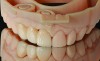

(7.) Completed restoration seated on a model reproduced from the optical impression.

Figure 7